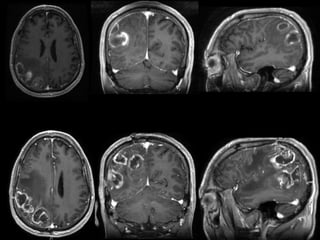

Radiological findings:

Ring-enhancing lesions

 Central necrotic área

 Enhancing rim (active tumoral cells)

 Severe perilesional edema

 Radiological visualization of the invasive front is difficult

 Tend to underestimate the extent of diffuse inflitrative

glioma growth.

 Multifocal gliomas: multiple lesions that come from an original

lesion. Usually located in the same brain hemisphere.

 Multicentric gliomas: multiple lesions not originated from the

same lesion.Widely separated.

Radiological findings: Ring-enhancing lesions Central necrotic área  Enhancing rim (active tumoral cells)  Severe perilesional edema  Radiological visualization of the invasive front is difficult  Tend to underestimate the extent of diffuse inflitrative glioma growth.

Radiological findings:  Multifocalgliomas: multiple lesions that come from an original lesion. Usually located in the same brain hemisphere.  Multicentric gliomas: multiple lesions not originated from the same lesion.Widely separated.